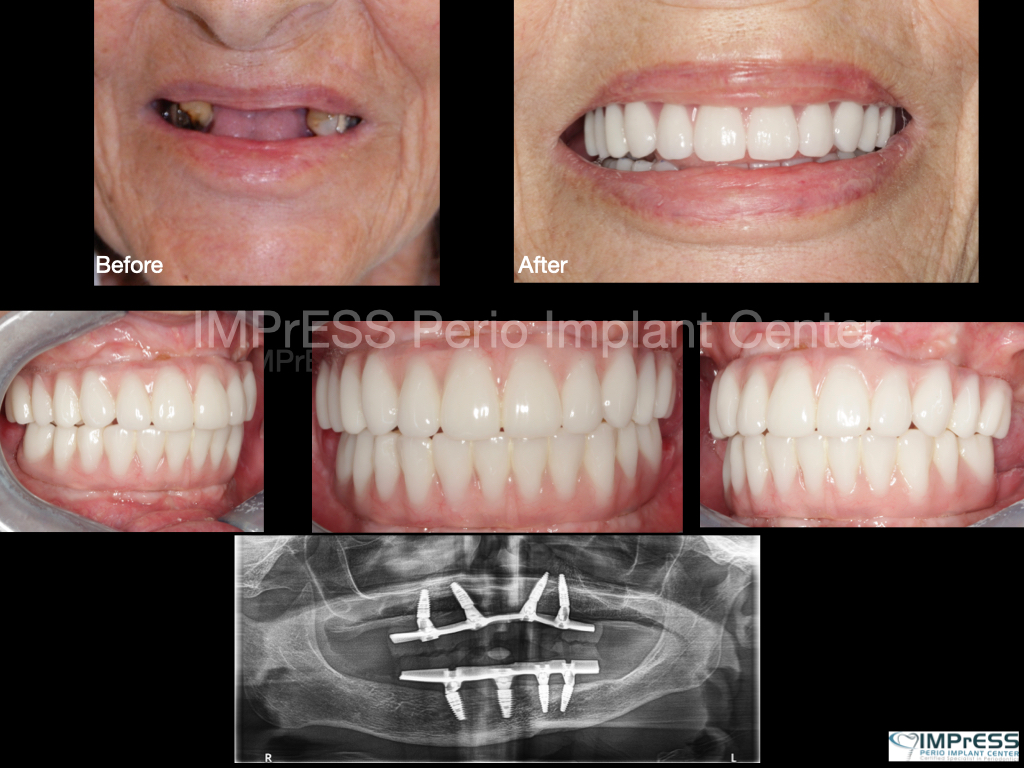

CBCT Guided Implant Surgery – Restoratively Driven Implants